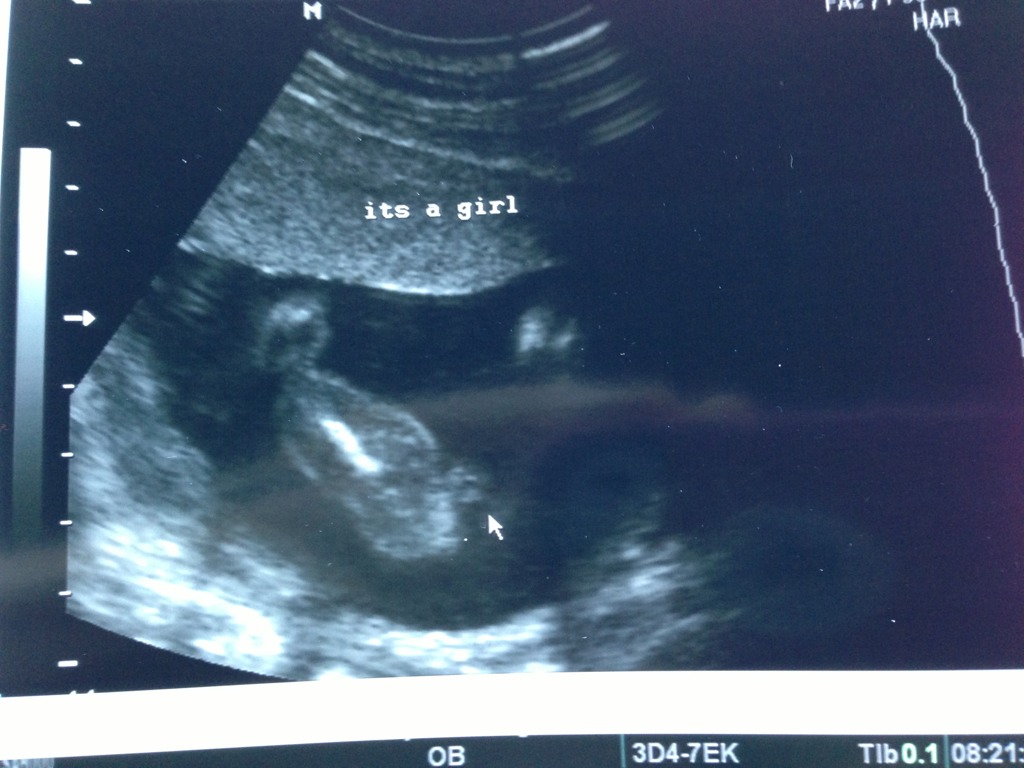

Told girl at 14 weeks and again at 19 weeks

Baby girl..